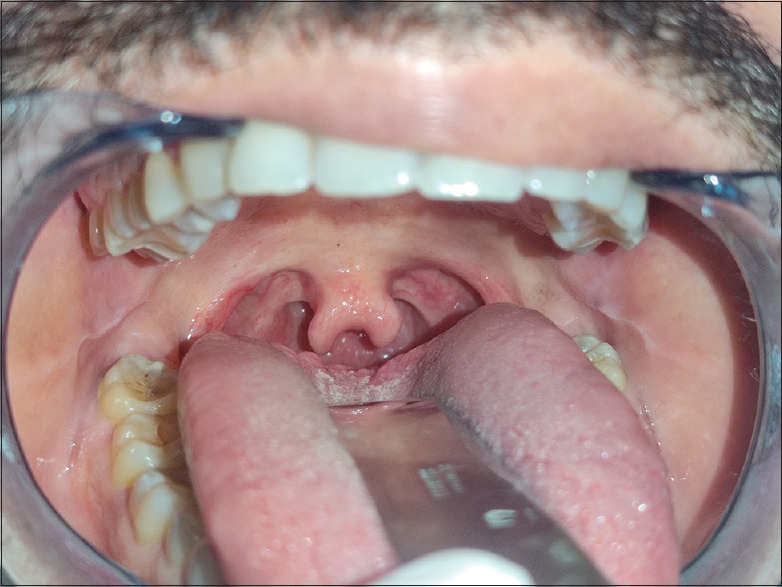

案例1:一名八岁的男孩在一家私人牙科诊所进行口腔筛查时,他的母亲陪同前来,她是为了自己的牙科治疗而来。在诊查中偶然发现,这名孩子患有D型双裂小舌[图1]。这个孩子是足月出生的,通常产程正常,没有其他相关的历史。没有同近亲的婚姻史。这个孩子是在足月怀孕后正常分娩的。进一步检查时,未发现唇裂或腭裂。

案例2:一名44岁的男性没有相关家族病史,前来私人诊所进行口腔筛查,偶然被诊断出患有双裂小舌(C型)[图2]。牙医在口腔面部复合体中未发现任何其他相关的体征和症状。此外,家族谱中没有报道有人患有双裂小舌。这名成年男子在成长过程中没有记得有任何言语或吞咽困难。